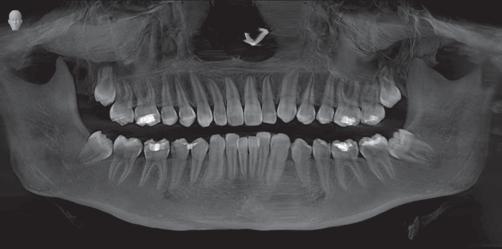

Do I really need to remove my wisdom teeth, they don’t hurt?

Through the studies of ancient tribes there was a time where one’s jaws were big enough to accommodate 32 teeth. Through environment and dietary changes we no longer have room for the third set of molars, also called wisdom teeth. When these teeth cannot erupt in to the mouth correctly they often become “impacted” or stuck in a crooked position. This impaction causes several problems which are not always painful including:

• Damage to other teeth: by crowding and pushing other teeth causing pain and bite problems

• Jaw damage: cysts can form around the third molars causing bone loss and damage to the nerve

• Sinus Issues: pain, pressure and congestion

• Inflamed gums: tissue can swell and may be hard to keep clean & lead to gum infection

• Cavities: swollen, infected gums can create pockets between teeth that help bacteria form and cavities will develop

• Alignment: the third molars can cause crowding and create the need for orthodontics to straighten teeth for a healthy smile

• Vertigo: commonly known as dizziness which is caused by the pressure of the wisdom teeth on the nerve which leads to the ear, which also controls one’s balance The jaw bone has no feeling other than the nerve that runs through it and connects to teeth from under the roots; unless your problem affects the actual nerve you may have no pain but that does not mean there is no problem-not yet!

Wisdom Teeth: Is it wise to keep them?

Wisdom teeth or third molars are the last permanent molars to erupt in the mouth. They usually appear between the ages of 17 to 25 but can grow any time after that. We don’t usually use those teeth for chewing because they are so far back in the mouth. Third molars are hard to keep clean and very prone to decay.

Misaligned wisdom tooth that caused patient to lose both teeth. Impacted Wisdom teeth.